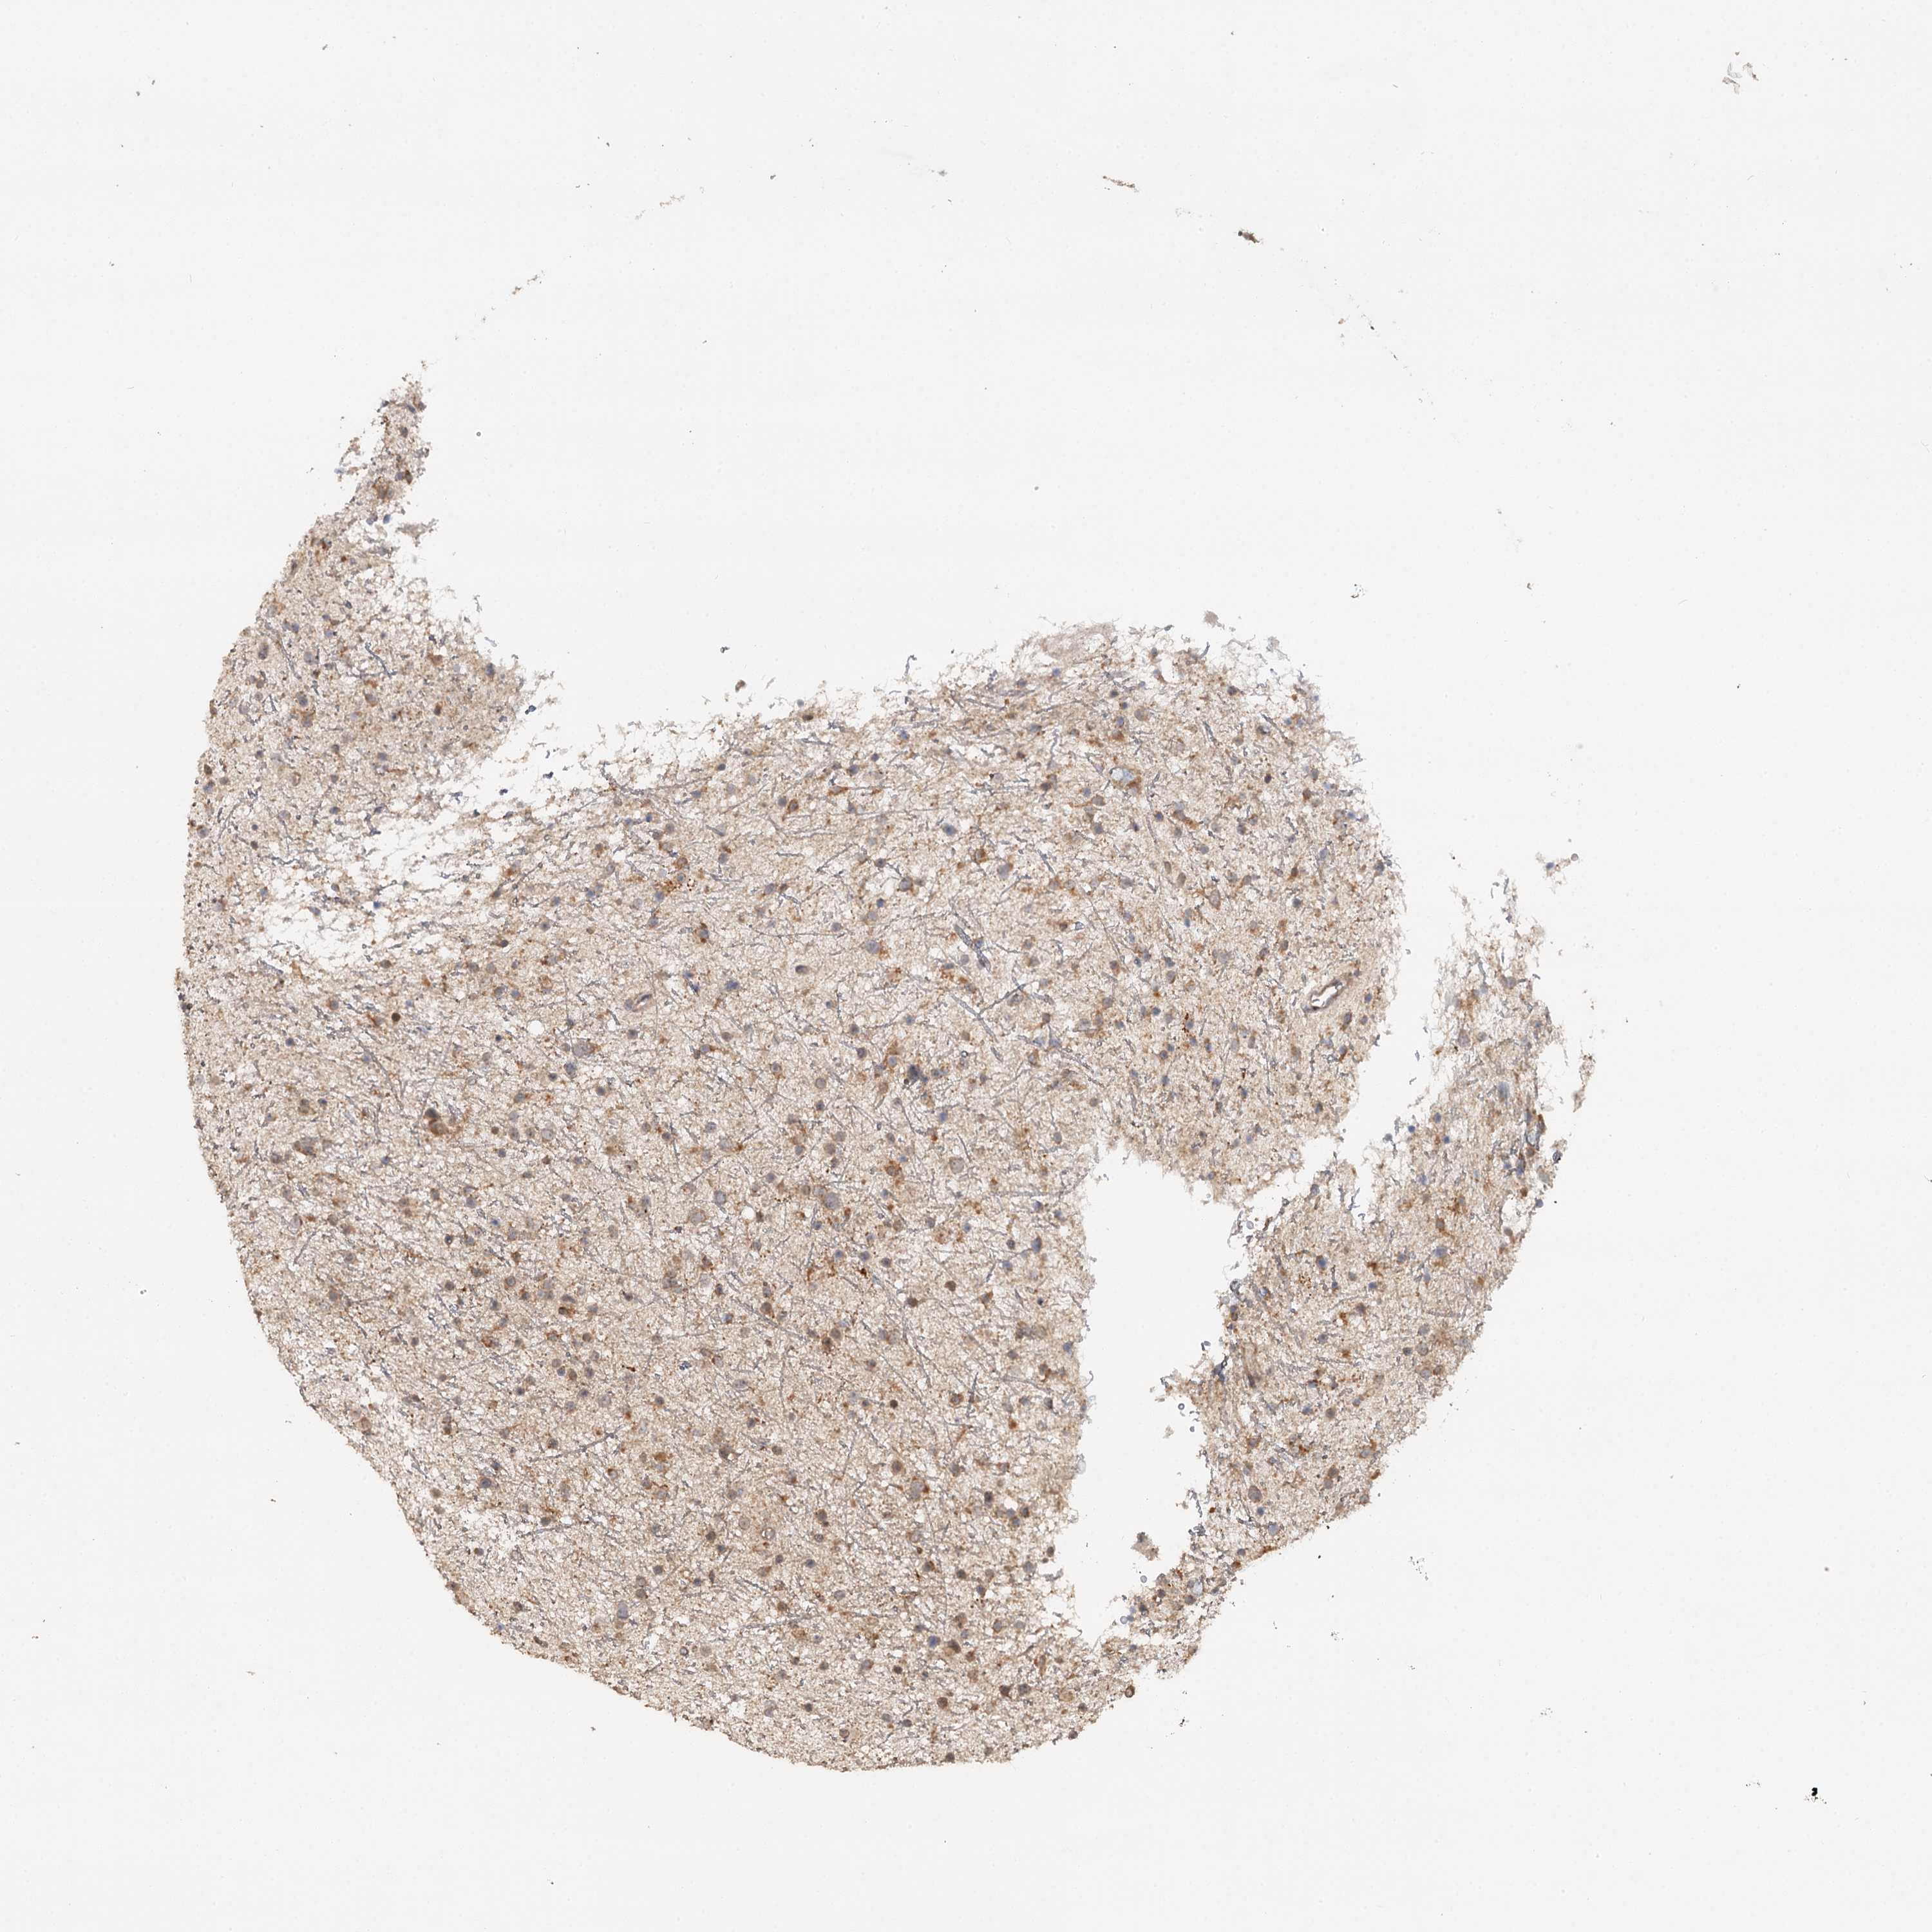

GLIOMA - Protein expressioni

A mouse-over function shows sample information and annotation data. Click on an image to view it in a full screen mode. Samples can be filtered based on level of antibody staining by selecting one or several of the following categories: high, medium, low and not detected. The assay and annotation is described here.

Note that samples used for immunohistochemistry by the Human Protein Atlas do not correspond to samples in the TCGA dataset.

Antibody stainingi

Antibody staining in the annotated cell types in the current human tissue is reported as not detected, low, medium, or high, based on conventional immunohistochemistry profiling in selected tissues. This score is based on the combination of the staining intensity and fraction of stained cells.

Each image is clickable and will lead to virtual microscopy that enables deeper exploration of all samples and also displays staining intensity scores, fraction scores and subcellular localization as well as patient and tissue information for each sample.

Antibody HPA039106

Staining

High

Medium

Low

Not detected

Intensity

Strong

Moderate

Weak

Negative

Quantity

>75%

75%-25%

<25%

None

Location

Nuclear

Cytoplasmic/membranous

Cytoplasmic/membranous,nuclear

Glioma, malignant, High grade

Glioma, malignant, Low grade

Glioblastoma, NOS